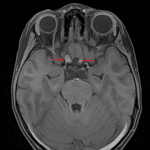

Age: 4

Sex: Female

Indication: History of neurofibromatosis type 1

- Mild expansion and enhancement of the right greater than left prechiasmatic optic nerves and optic chiasm, likely representing optic pathway glioma

- Patchy, minimally expansile T2/FLAIR signal hyperintensity involving the anterior commissure, left forniceal column, bilateral deep gray structures, brainstem, and left greater than right cerebellar white matter without corresponding restricted diffusion or enhancement, which may represent focal areas of signal intensity (FASI) and/or infiltrative glioma

- Left persistent trigeminal artery

- Developmental venous anomaly involving the right frontal operculum

Optic pathway glioma